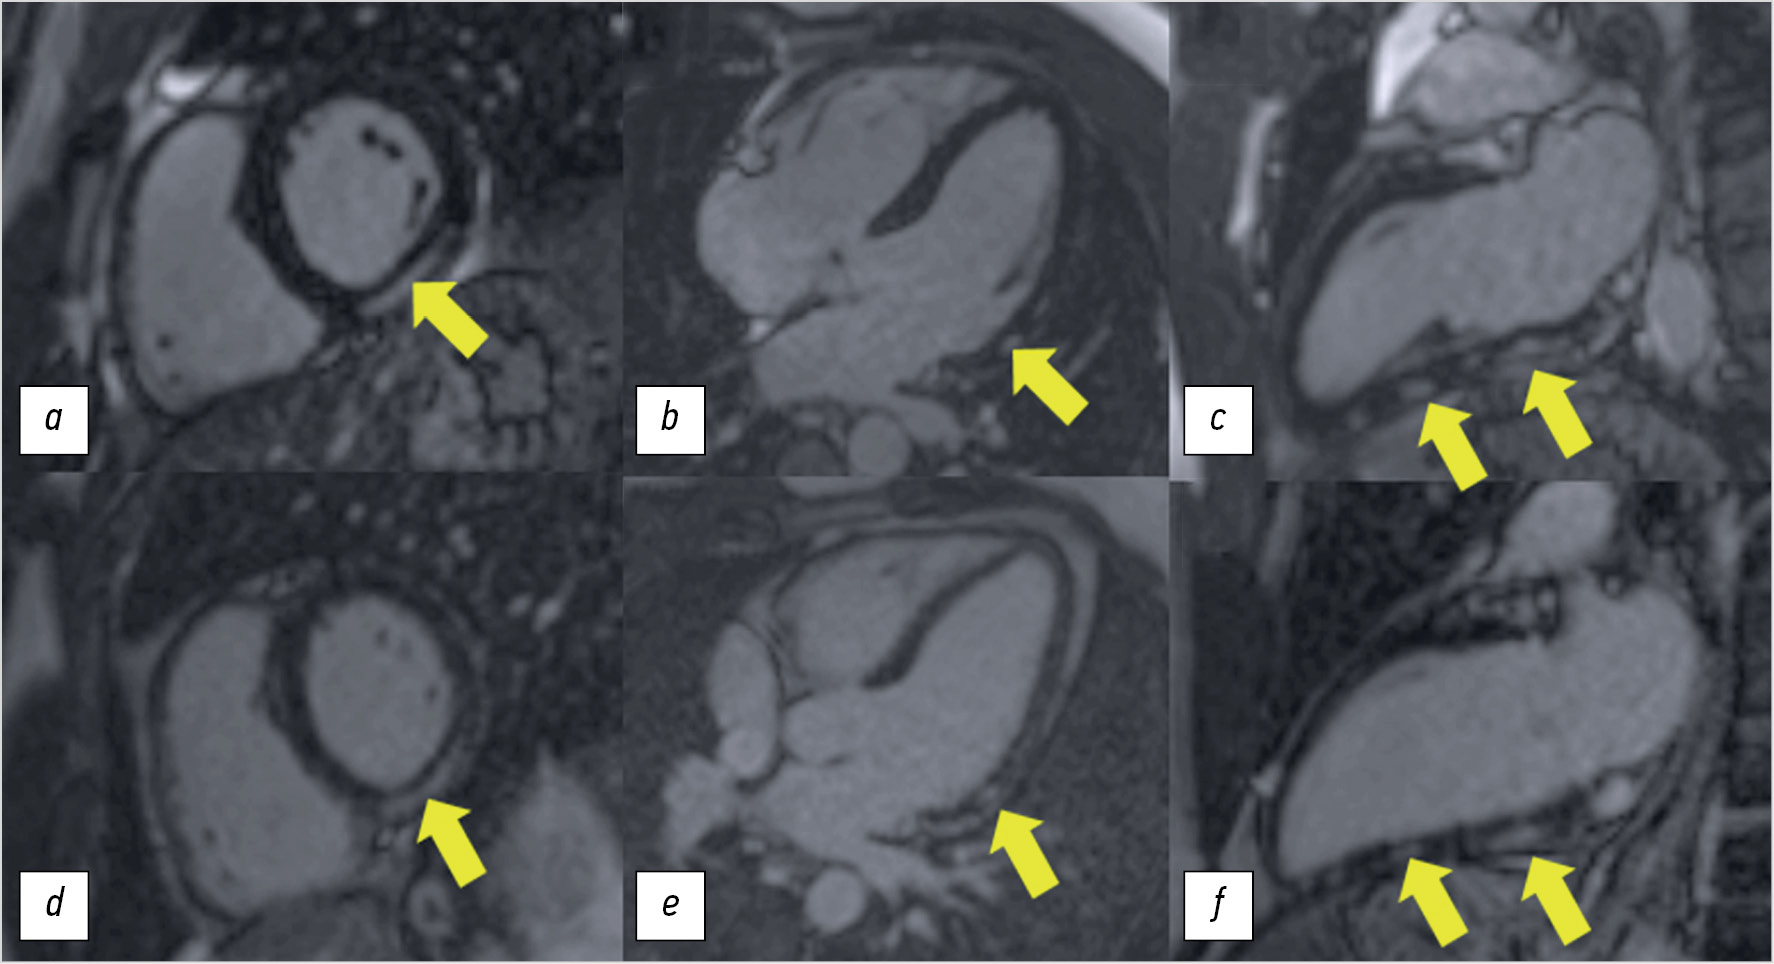

Signs of myocardial inflammation were noted including areas of early and delayed contrast enhancement in the basal and middle lateral and lower segments with the transition to the apical lower segment of the left ventricle (Figure 4a–c), as well as signs of myocardial edema in these segments (Figure 5a).

Fig. 4. Magnetic resonance imaging of the heart in delayed contrast mode with a gadolinium-containing contrast agent (7–15 minutes after administration of the contrast agent), pulse sequence Flash 2D Inversion Recovery: a, d — short axis of the left ventricle in the basal segments; b, e — long axis of the left ventricle, four-chamber view; c, f — long axis of the left ventricle, two-chamber view. Top row, a–c — magnetic resonance imaging of the heart initially: in the basal and middle lateral and inferior segments with a transition to the apical inferior segment of the left ventricle, subepicardial areas of contrast are noted (yellow arrows); bottom row, d–f — dynamic magnetic resonance imaging of the heart after 1.5 months: areas of delayed contrast of the previous localization and intensity remain.

After 1.5 months, the contrast-enhanced MRI of the heart showed that the area of subepicardial delayed enhancement of the previous extent remained in the basal and middle inferior segments (Figure 4d–f), and no evidence of myocardial edema was found in these segments (Figure 5b).

In this case report, contrast-enhanced cardiac MRI confirmed the clinical diagnosis. According to cardiac MRI, the patient initially had one of the above criteria for diagnosing myocarditis (myocardial edema on T2 mapping and evidence of non-ischemic myocardial injury on delayed gadolinium enhancement). MRI performed after 1.5 months showed no signs of myocardial edema, indicating a decrease in acute myocardial inflammation.